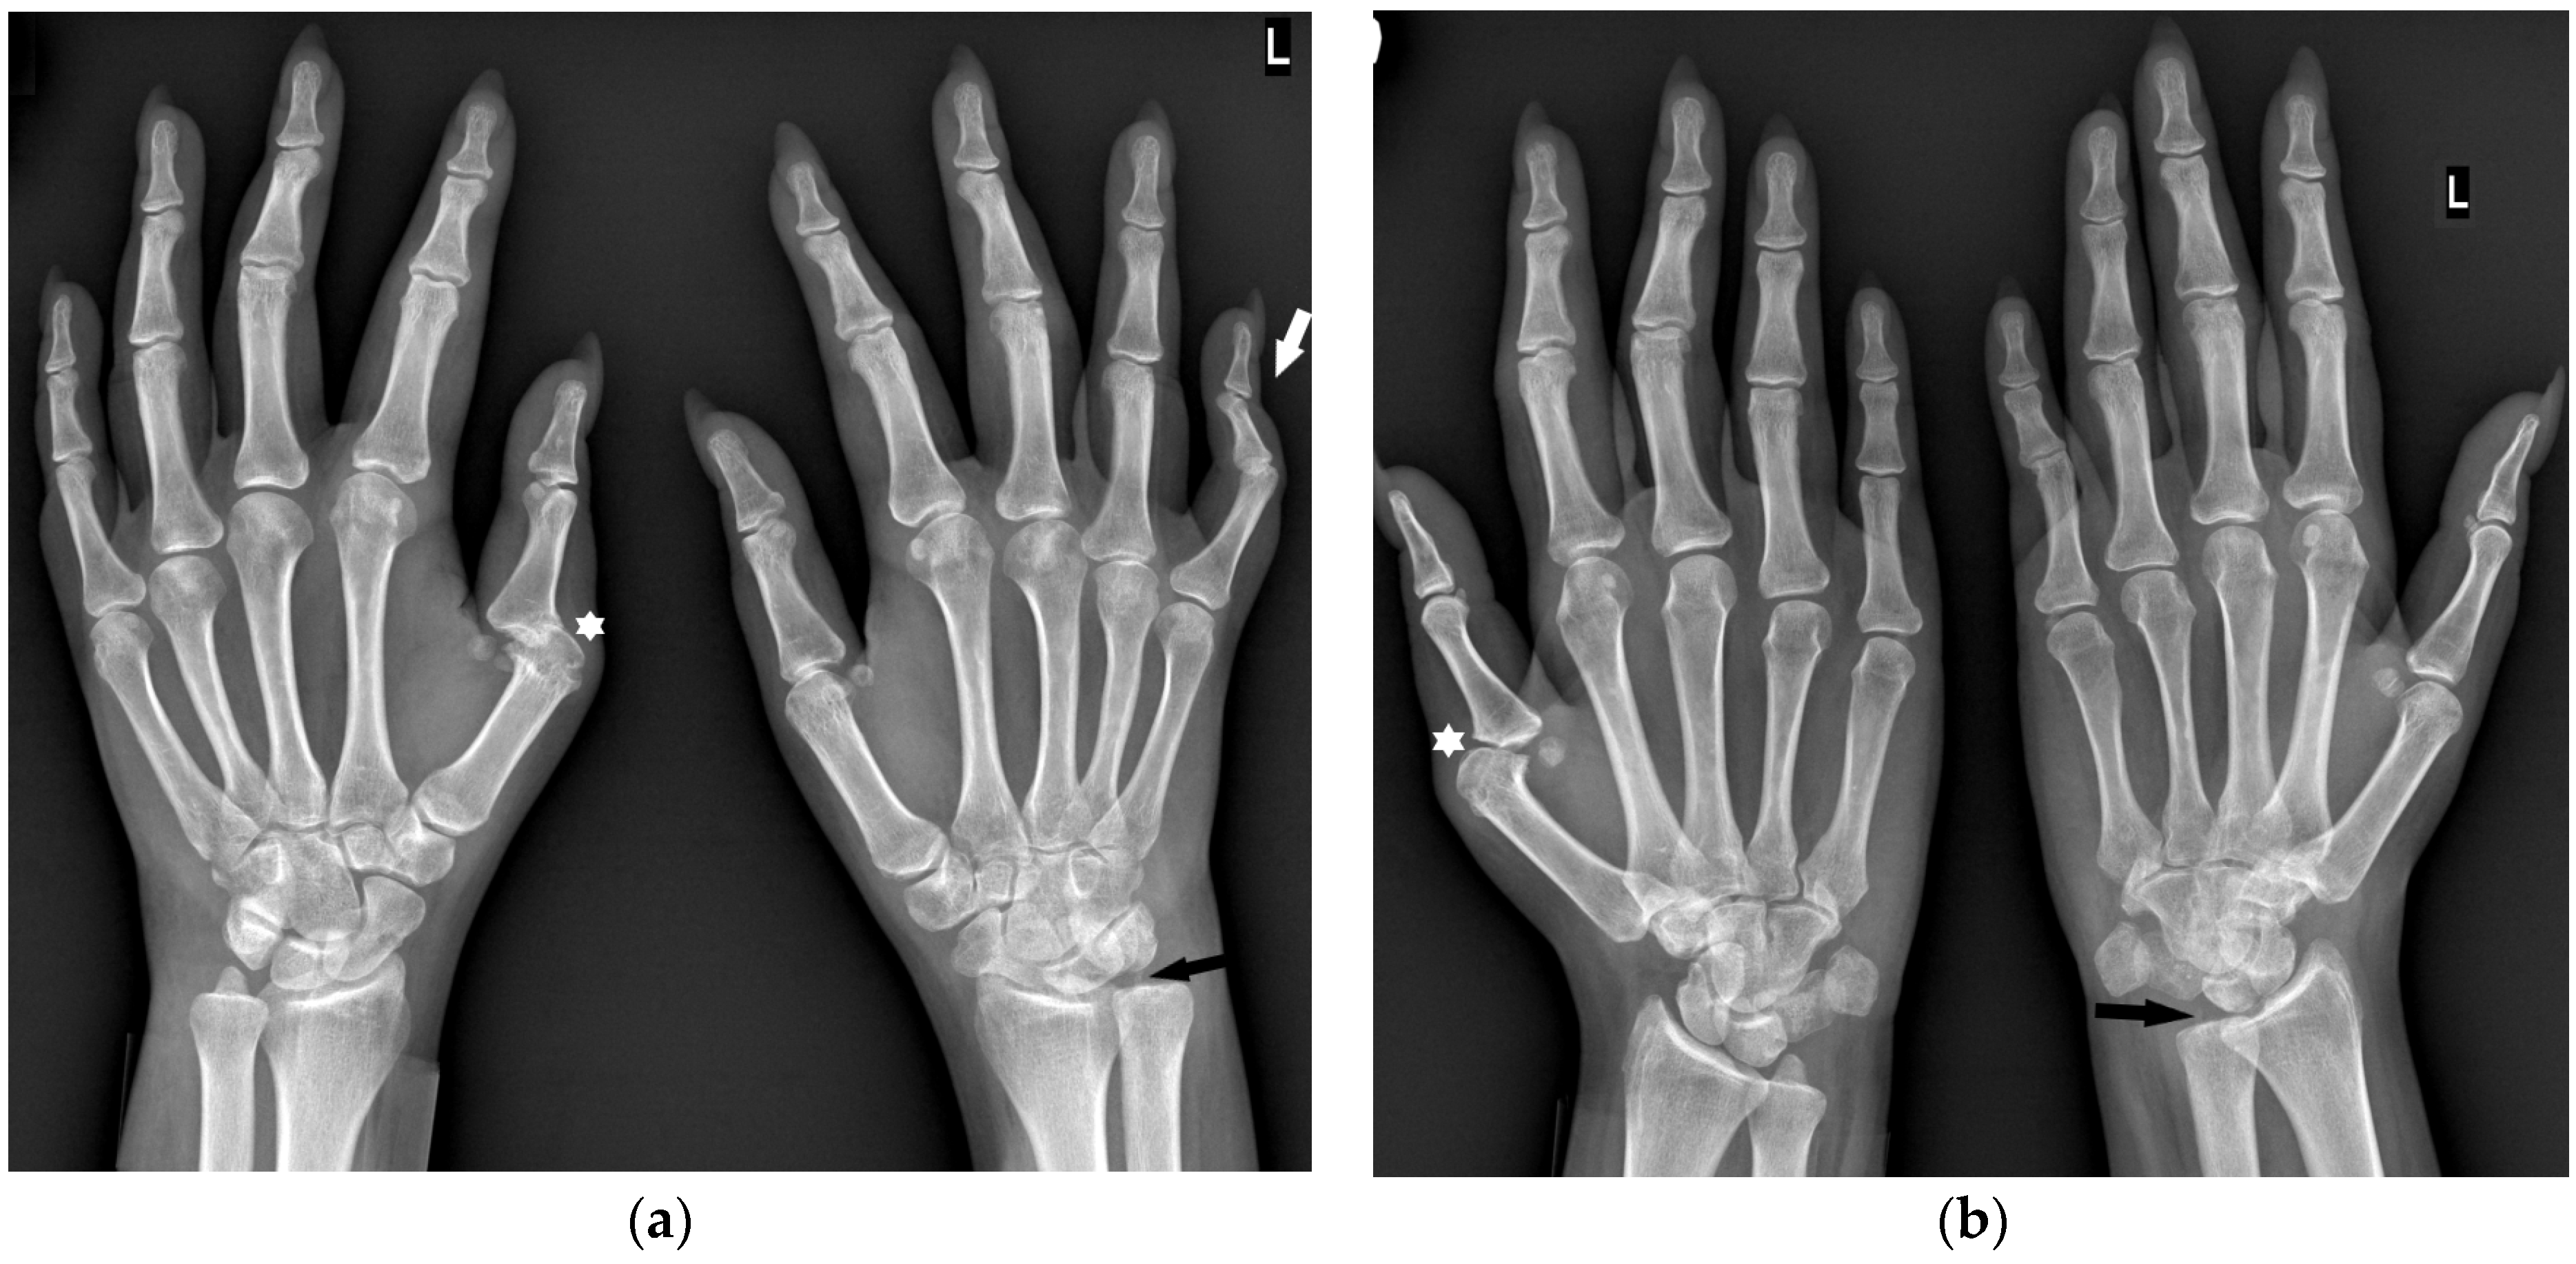

‘Seronegative RA’ is the least understood entity and only a few scientific studies describe the radiological image of this form. In a study by Gadelholt et al. [16], seronegative RA patients predominantly displayed carpal damage (Figure 3) with less-affected PIP joints and relative sparing of the feet compared with seropositive RA. Erosions and joint space narrowing were more prominent in seropositive RA, resulting in an overall higher disease activity score.

Figure 3.

A 30-year-old female with seronegative RA. PA (a) and Nørgaard radiographs (b) of bilateral hands. Note the boutonnière deformities, most prominent in the left small finger (white arrow). There is left RCJ space narrowing with scattered bone cysts and chronic deformity of the scaphoid bone. Note the osteolysis of the left ulnar styloid process (black arrow). Scattered bone cysts are observed in the right carpal bones. Note the erosive changes and bone cysts in the right first MC head with subluxation of the MCP joint (star).